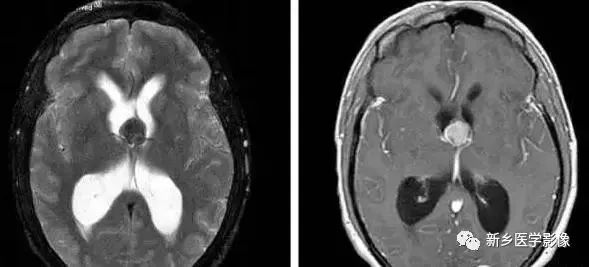

❹ 一侧室间孔阻塞

脑脊液主要产生于脑室的脉络膜丛。当一侧室间孔阻塞时,同侧侧脑室脉络膜丛产生的脑脊液不能进入三脑室,脑脊液在侧脑室内聚积,CT和MR检查表现为一侧侧脑室扩大,扩大明显时可有中线结构向对侧移位,主要原因有室间孔附近的肿瘤、囊肿、囊虫及炎性粘连。

确定一侧侧脑室扩大为室间孔阻塞所致的要点包括:

- 一侧侧脑室扩张明显,有张力;

- 透明隔向对侧移位;

- 扩一大的侧脑室周围没有能够导致该侧侧脑室扩大的其他可以解释的原因。